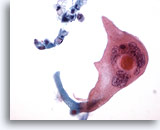

Figure 79

Bronchial wash

Numerous atypical squamous cells with polys are present in this cluster of cells from a case of squamous cell carcinoma. 20x

Bronchial wash

Numerous atypical squamous cells with polys are present in this cluster of cells from a case of squamous cell carcinoma. 20x

Figure 79

Bronchial wash

Numerous atypical squamous cells with polys are present in this cluster of cells from a case of squamous cell carcinoma.

20x

Bronchial wash

Numerous atypical squamous cells with polys are present in this cluster of cells from a case of squamous cell carcinoma.

20x